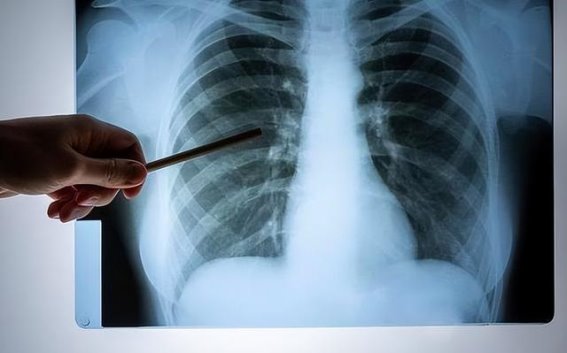

并不是所有口腔异常都意味着肺癌。许多常见的口腔问题,如口腔炎、牙周病等,并不一定与癌症有关。但如果口腔问题持续时间较长,尤其是伴随其他肺癌相关症状,应该尽早就医。尤其是长期吸烟、有肺癌家族史的人群,更应定期进行肺部检查。

如果你长期口臭、咳血、口腔溃疡、牙龈出血、口干舌燥、味觉异常等症状,尤其是症状持续两周以上没有缓解,建议及时就医检查,进行肺部低剂量螺旋CT等基础筛查。